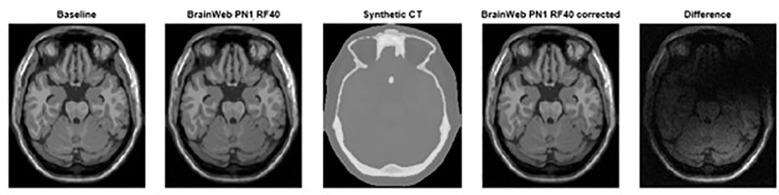

An unbiased simulated T1-Weighted MRI validated dataset is utilized to create a synthetic CT (sCT). By introducing controlled distortion in simulated datasets, we can evaluate the influence of noise and intensity non-uniformity ("RF") ranging from 0 to 9% noise and 0 to 40% RF. These MRIs were corrected using the sCT as base modality for distortion correction. To evaluate the impact of the distortion correction, each corrected/non-corrected image set was compared to the unbiased MRI using Root-mean-square-error (RMSE) as a full-image reference comparison metric.

利用一个无偏模拟T1加权MRI验证数据集创建合成CT(sCT)。通过在模拟数据集中引入可控失真,我们可以评估噪声和强度不均匀性(“RF”)在0至9%噪声和0至40%RF范围内的影响。这些MRI以sCT作为失真校正的基础模态进行校正。为评估失真校正的影响,使用均方根误差(RMSE)作为全图像参考比较指标,将每个校正/未校正的图像集与无偏MRI进行比较。